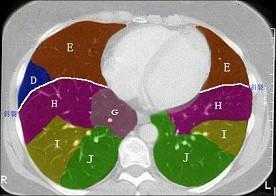

结合肺段模式肺动脉干与右肺动脉层面(见图),选出右肺中叶的组成 ( )A、D+EB、D+E+FC、B+CD、B+C+DE、B

问题 结合肺段模式肺动脉干与右肺动脉层面(见图),选出右肺中叶的组成 ( )

选项 A、D+E B、D+E+F C、B+C D、B+C+D E、B

答案 A